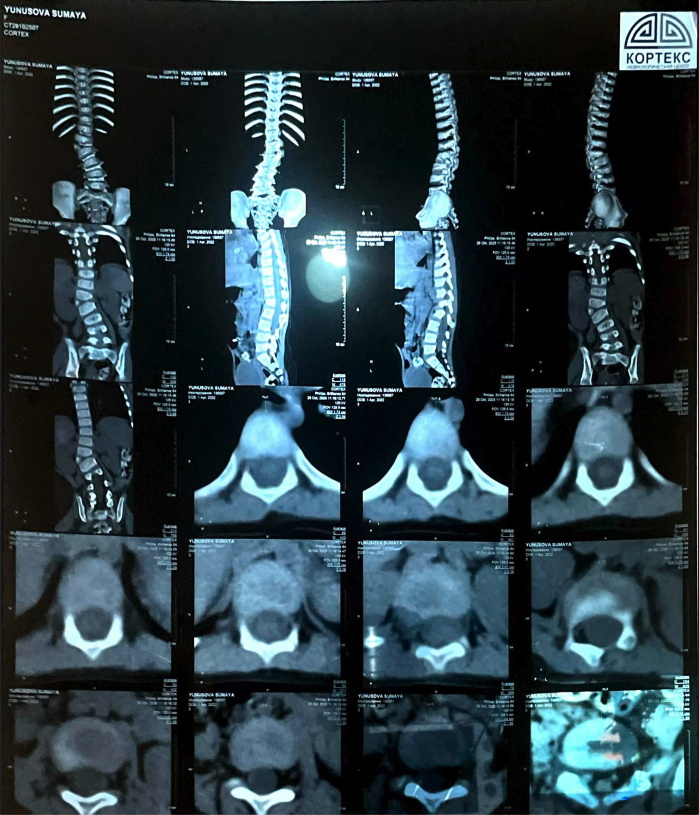

У нее сколиоз сложной формы. Из-за заболевания девочке трудно быстро ходить и бегать, поэтому большую часть времени она сидит или лежит.

"Поняв, что ничего не помогает, мы обратились к профессорам из Турции. Они считают, что единственное решение - это операция, и чем скорее ее проведем, тем лучше для дальнейшего роста и развития Сумаи. А недавно мы узнали еще, что у нее есть лишняя кость на позвонке (отросток видно на рентгеновском снимке). Это тоже следствие сколиоза", - говорит мама.

Искривление позвоночника уже привело к асимметрии тела, у малышки одно плечо стало ниже другого, а одна нога короче другой.